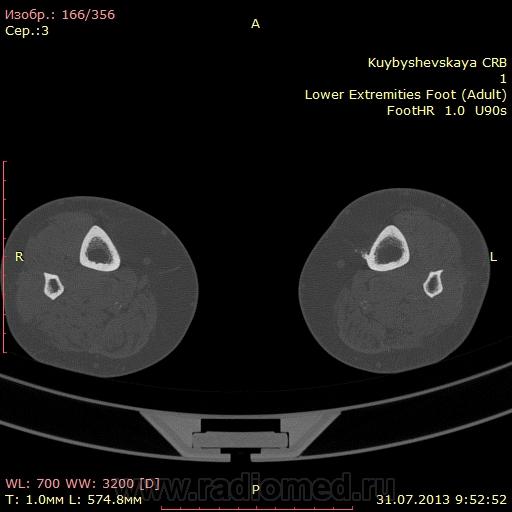

женщина. 69 лет. жалобы на боли в нижней трети голени слева в течении месяца. по снимкам врач написал периостит(к сожалению фотоаппарата нет под рукой)В ближайшее время травм не было. мне досталась только карточка. Пациента не видел. Помогите с диагностикой. вроде бы на зло не похоже. или ошибаюсь?

На зло непохоже, нет мягкоткотканного компонета. Передне-медиальная поверхность голени - самое место для травмы. Только термин "периостит" мне тоже не нравится, написал бы - локальное обызвествления мягких тканей, вероятнее всего посттравматического характера.

По снимкам описал бы как обызвествившуюся гематому, а по КТ больше тянет на экзостоз, только основание очень широкое.

Тем более не "зло". На боковом снимке, в захваченной стопе, р-признаки синдрома переднего большеберцово-таранного соударения. Она же стопа "футболиста" или спортсмена

Может "...в ближайшее время травм И не было...", но что его, наверняка, когда-то "подковывали" бутсой по передней поверхности голени, несомненно.